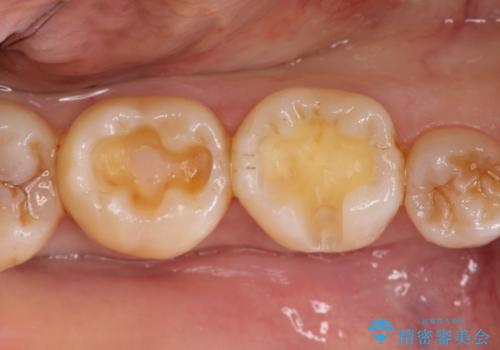

メタルインレーからセラミックインレーへ

- メタルインレーによる審美障害を主訴に来院されました。

セラミックインレーに治療を行っております。

e-max プレスインレーにて修復治療を行っているため適合性及び審美性の高い治療を行うことができます